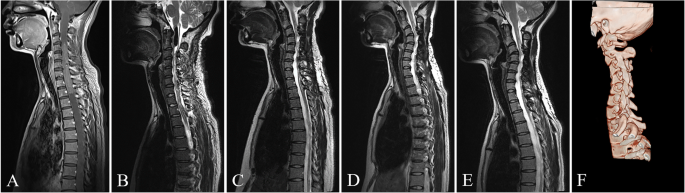

The T2-weighted MR images shown was a 30-year-old woman who underwent resection of the ependymoma spanning from C3 to T2. a Preoperative MR images showed a huge tumor and the cervical spine had lost its normal curvature. b Postoperative MR images during postoperative hospitalization showed complete resection of spinal cord tumor and almost no change in cervical curvature. c The follow-up MR image showed progressive cervical kyphosis 6 months after the operation. d, e The follow-up MR image showed deterioration of progressive cervical kyphosis 13 months and 24 months after the operation, respectively. f The CT three-dimensional reconstruction image showed the cervical kyphosis 24 months after the operation. At that time, the patient complained that her left upper limb was numb